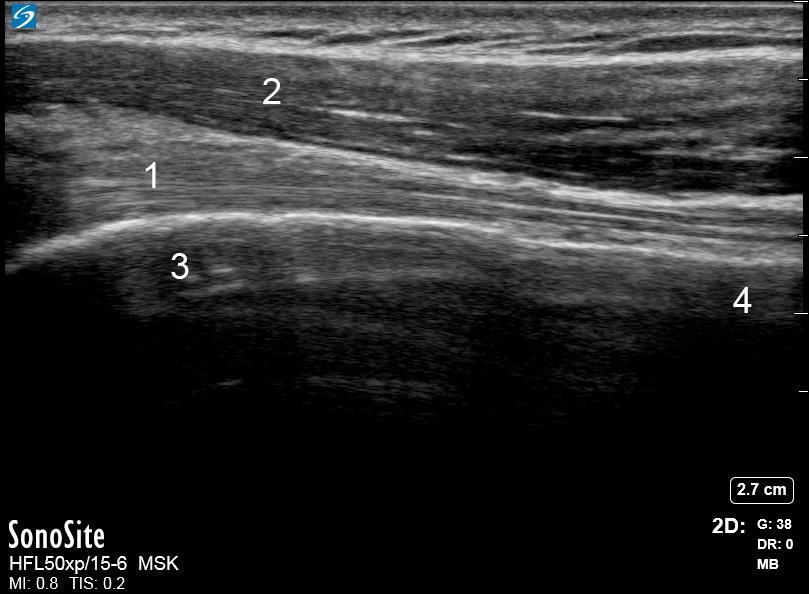

Shoulder Anterior Biceps Tendon Long Axis Image

1. Bicep Tendon

2. Anterior Deltoid Muscle

3. Humeral Head

4. Humeral Neck